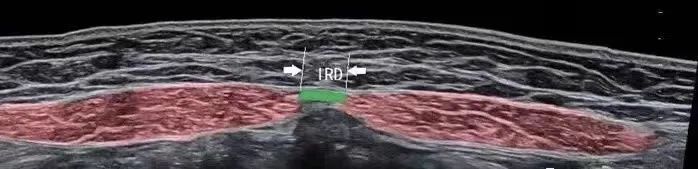

高频超声检测使用高频超声探头测量DRA,较之传统手法检查具有操作简便、图像直观、快速准确、高度可重复性、经济安全、灵敏度高、漏诊率低、患者容易接受等优点,是对孕妇妊娠期DRA程度精准检测、产程中产妇DRA监测以及产妇产后DRA评价的首选影像学检查方法。

从图像来看,腹直肌分离的影像特征表现为前腹壁皮下脂肪层变薄,腹白线增宽,双侧腹直肌对称分离,双侧腹直肌前鞘变薄,朝两侧分离,腹直肌拉长、变薄,脐水平前腹壁局部前突等。